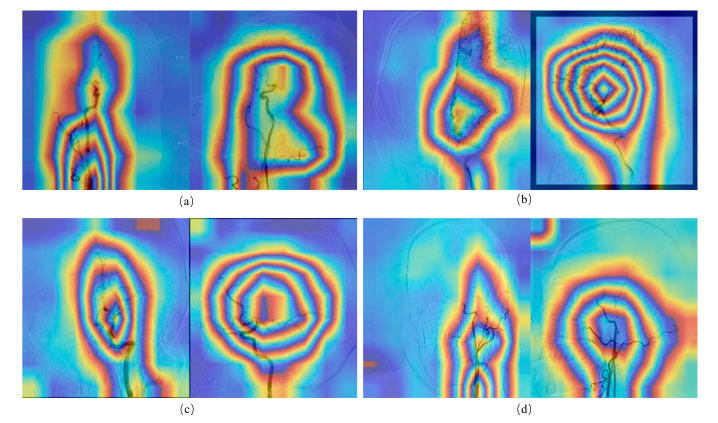

Fig. 4. Overall schematic diagram of CVFSNet and CVFM.

图4:跨视图融合评分网络(CVFSNet)以及跨视图融合模块(CVFM)的整体示意图。